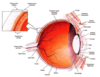

Pituitary - general parts

Lighter top region is pars nervosa, darker bottom region is pars distalis, middle is pars intermedia

Pituitary - remnants of Rathke’s pouch

At pars intermedia, the circles are remnants of Rathke’s pouch

Pars nervosa of pituitary consists of neuropil, pituicytes, endothelial cells, fenestrated capillaries, Herring bodies

Pars nervosa: neuropil is wispy material, most nuclei belong to pituicytes, some endothelial cells near RBC, fenestrated capillaries, identifying feature: pink blob called Herring bodies

Pars distalis of pituitary: Chromophobes, Basophils, Acidophils

Pars distalis: Chromophobes (don’t stain very intensely, not much color, already released all their hormones). Basophils (stain very dark, basophilic), Acidophils (stains very eosinophilic). Diff regions of pars distalis will have diff proportions of these 3 cell types

Pituitary - pars distalis and pars nervosa

Pars distalis is colorful. Lighter staining pars nervosa.

Pituitary - Pars intermedia

Pars intermedia: remnants of Rathke’s pouch